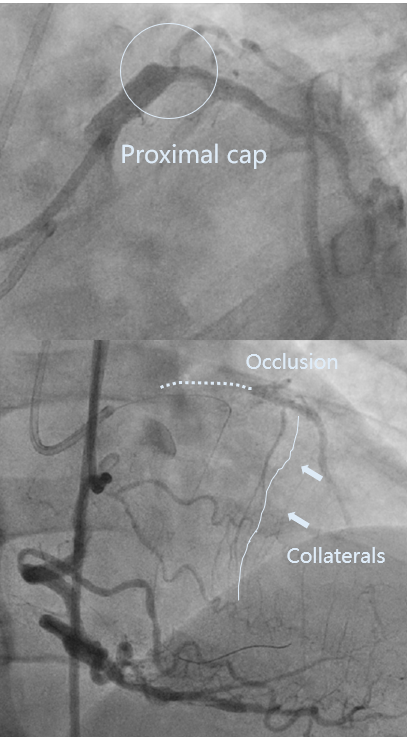

LAD开口全闭、OM开口70%

LM未见狭窄、LCX近中段40-50%狭窄

RCA 近段 60%、中段重度迂曲

LAD开口全闭、CTA示LAD严重钙化、RCA重度迂曲、外院尝试两次开通。

LAD pre-IVUS check RUN 1 looking for entry point

对侧造影提示导丝行至内膜下